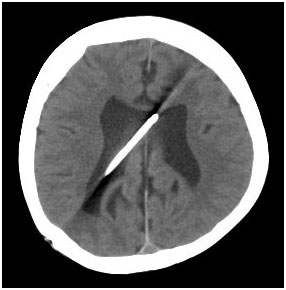

However, since the patient developed abdominal fluid recollection during the follow up, the distal VP shunt tip was subjected to external drainage [Table/Fig-2]. The culture showed no growth and the abdominal distension was reduced. The distal shunt tip was placed into the right atrium. The distal tip of the ventriculoatrial catheter (Codman, HOLTER Distal Atrial Catheter, Type E) was inserted into the right atrium via right internal jugular vein [Table/Fig-3]. The patient displayed no complications in the postoperative period and was discharged at 7th day. The follow-up echocardiographs showed no sign of problem.

Cranial CT before external drainaging of the shunt there is no extensive hydrocephalus